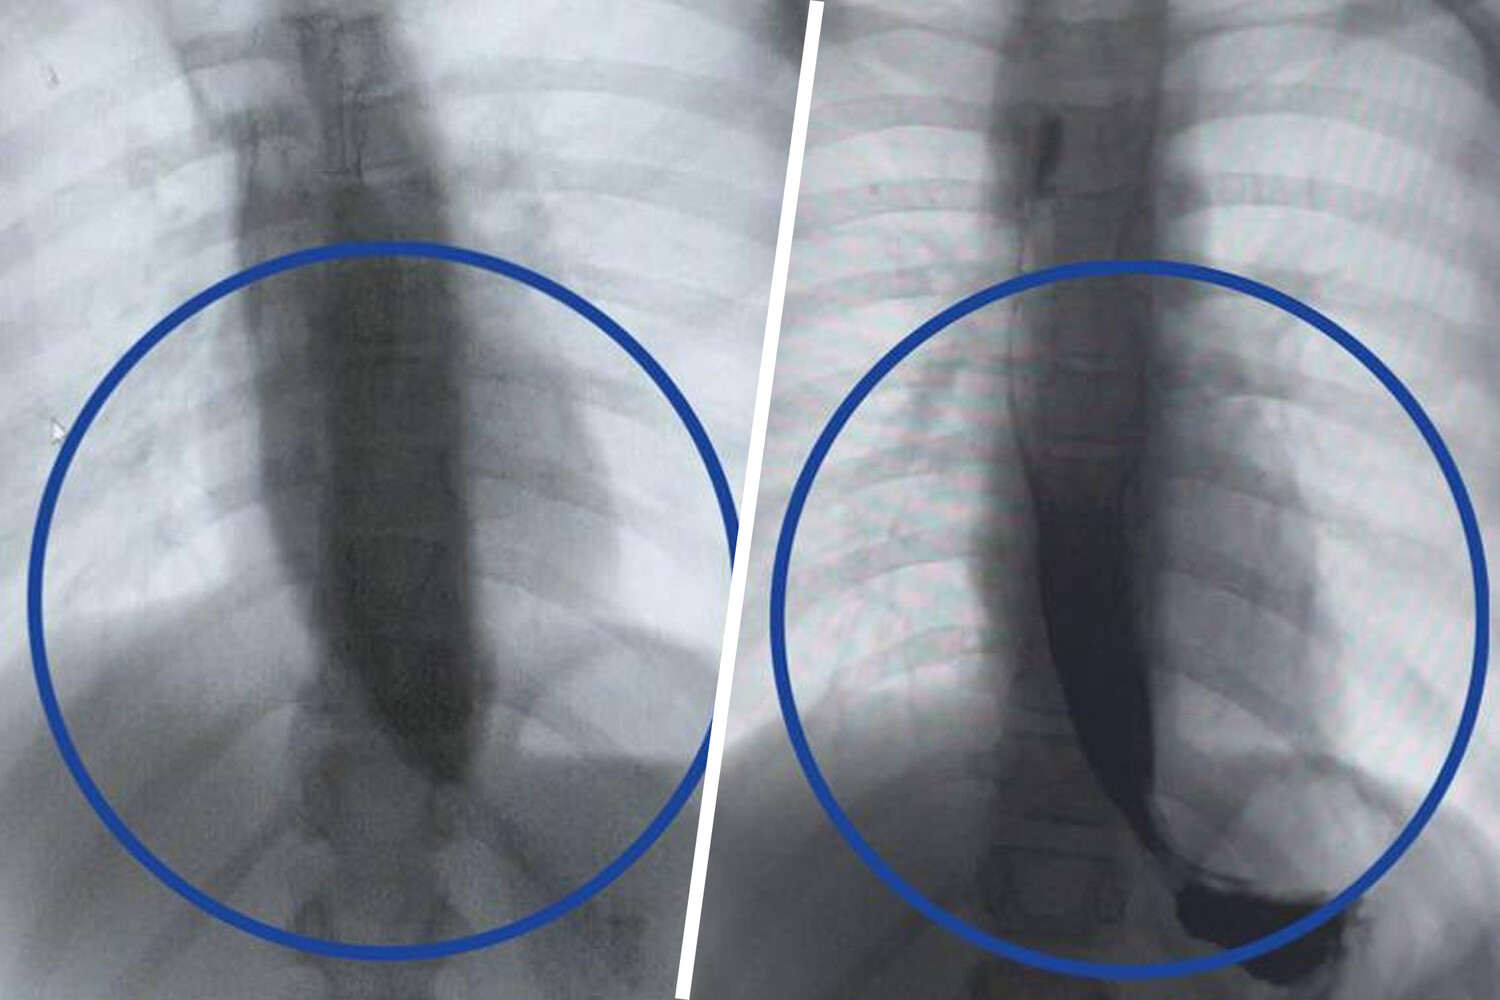

Врачи Детского клинического центра им. Л.М. Рошаля спасли девятилетнюю девочку с редким заболеванием — ахалазией кардии, из-за которого ее пищевод был расширен в пять раз. Об этом сообщили в пресс-службе минздрава Московской области.

Медики рассказали, что пищевод пациентки из-за патологии был расширен до четырех сантиметров, при норме в семь — десять миллиметров.

«Мы через разрез в пищеводе создали подслизистый туннель и рассекли циркулярные мышцы, блокирующие проход пищи», — поделился заведующий отделением эндоскопических методов диагностики больницы Александр Иноземцев.

Операция прошла успешно, что уже на следующий день показало контрастное исследование — пища стала беспрепятственно поступать в желудок.